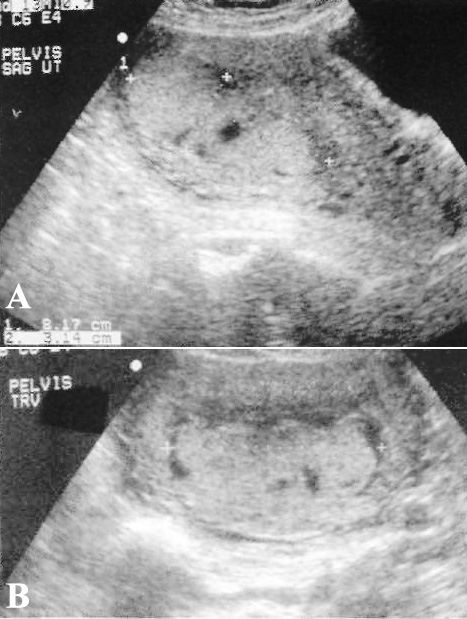

Ультразвуковое исследование позволяет выявить тромбофлебит овариальных вен. При этом врач должен оценивать клиническую картину (боли и температура тела). Нужно оценить предполагаемый ход овариальных вен, расположенных от областей придатков, кпереди от поясничных мышц, к участку слияния правой овариальной вены и нижней полой вены или левой вены с левой почечной веной. На УЗИ острый тромб представляет собой, как правило, гипоэхогенную структуру, которая растягивает вену (фото 2); со временем тромб становится более гетерогенным и эхогенным. Отметим, что диагностика может быть затруднена из-за увеличения послеродовой матки, ощущения дискомфорта у пациентки, а также возможной кишечной непроходимостью.

Фото 2. Тромбофлебит овариальной вены. А – УЗИ в сагиттальной плоскости. B – УЗИ в поперечной плоскости. На снимках УЗИ стрелками обозначена растянутая вена правого яичника. С – снимок КТ, на котором подтверждается тромбоз правой овариальной вены (обозначен стрелкой)